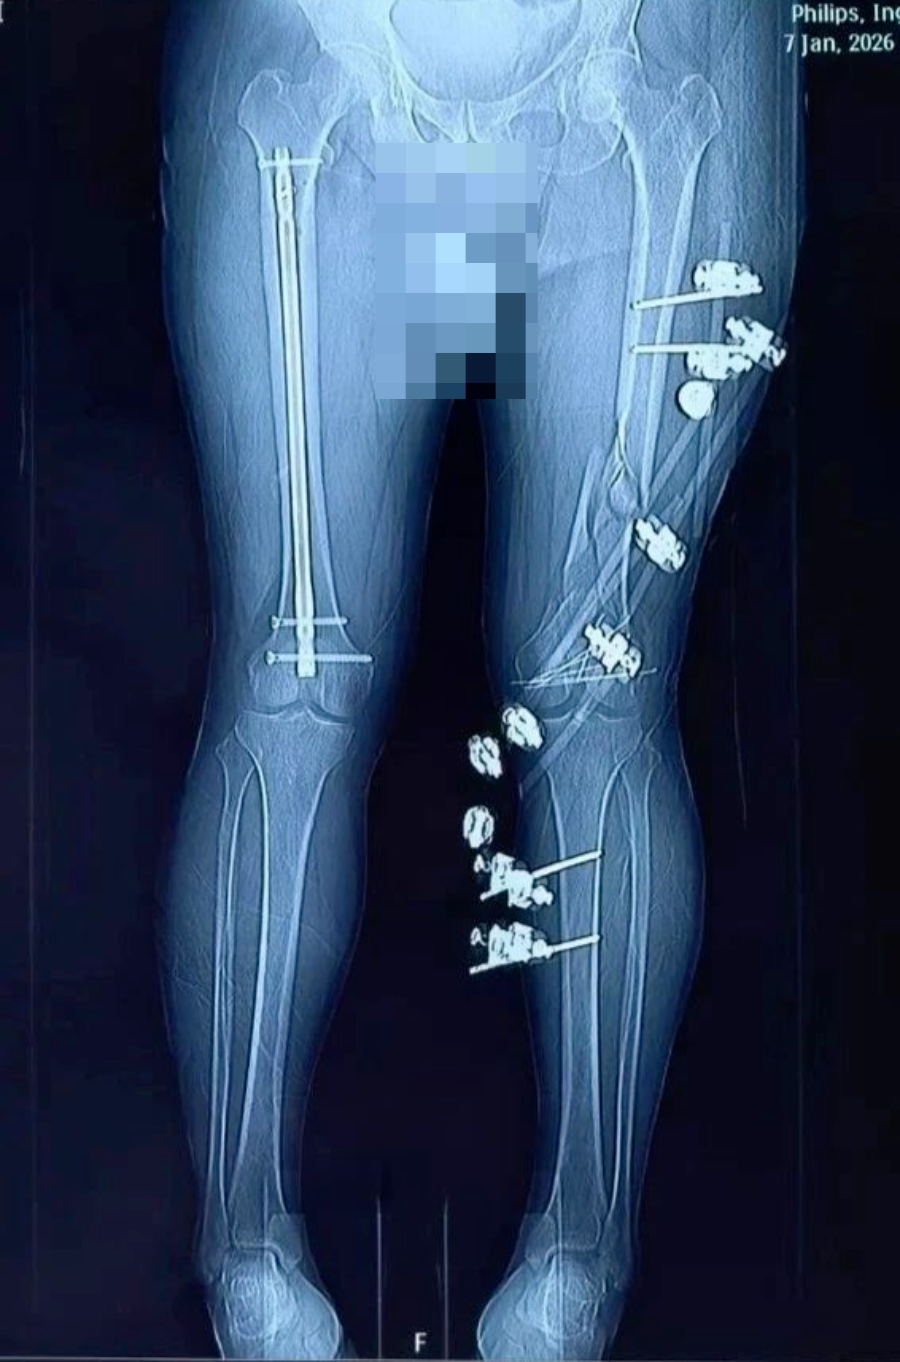

术后

抢救团队凭借丰富的创伤救治经验,在黄金时间内完成伤情评估与抗休克治疗。随后为患者施行骨折复位外固定、髓内钉内固定、解剖钢板内固定等关键手术治疗。手术过程顺利,患者出血得到有效控制,骨折部位获得稳定固定,术后生命体征平稳,安全转入ICU接受进一步监护与支持治疗。